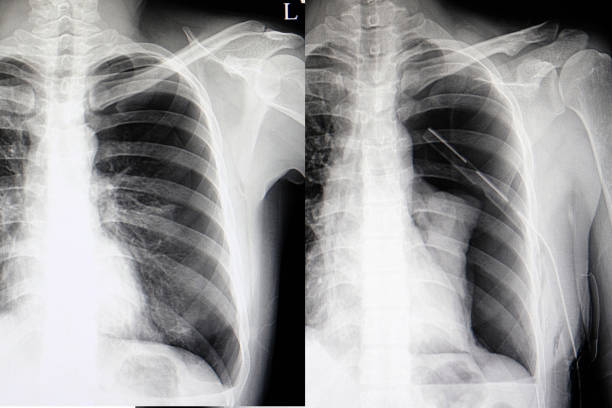

흉부 X선 검사

기흉이 의심되는 환자에게는 흉부 X선 검사를 실시하여 기흉이 있는지 확인할 수 있습니다. 이 방법은 비교적 쉽고 빠르게 기흉을 진단할 수 있습니다.